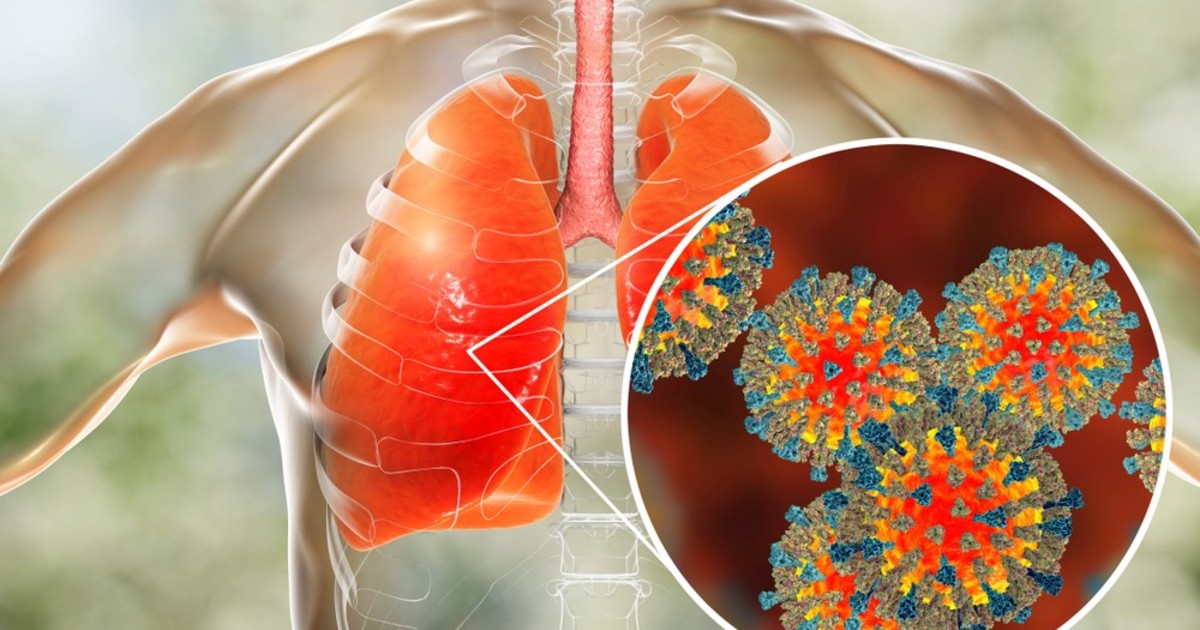

Фотографии бактерий, вызывающих бактериальные пневмонии у животных